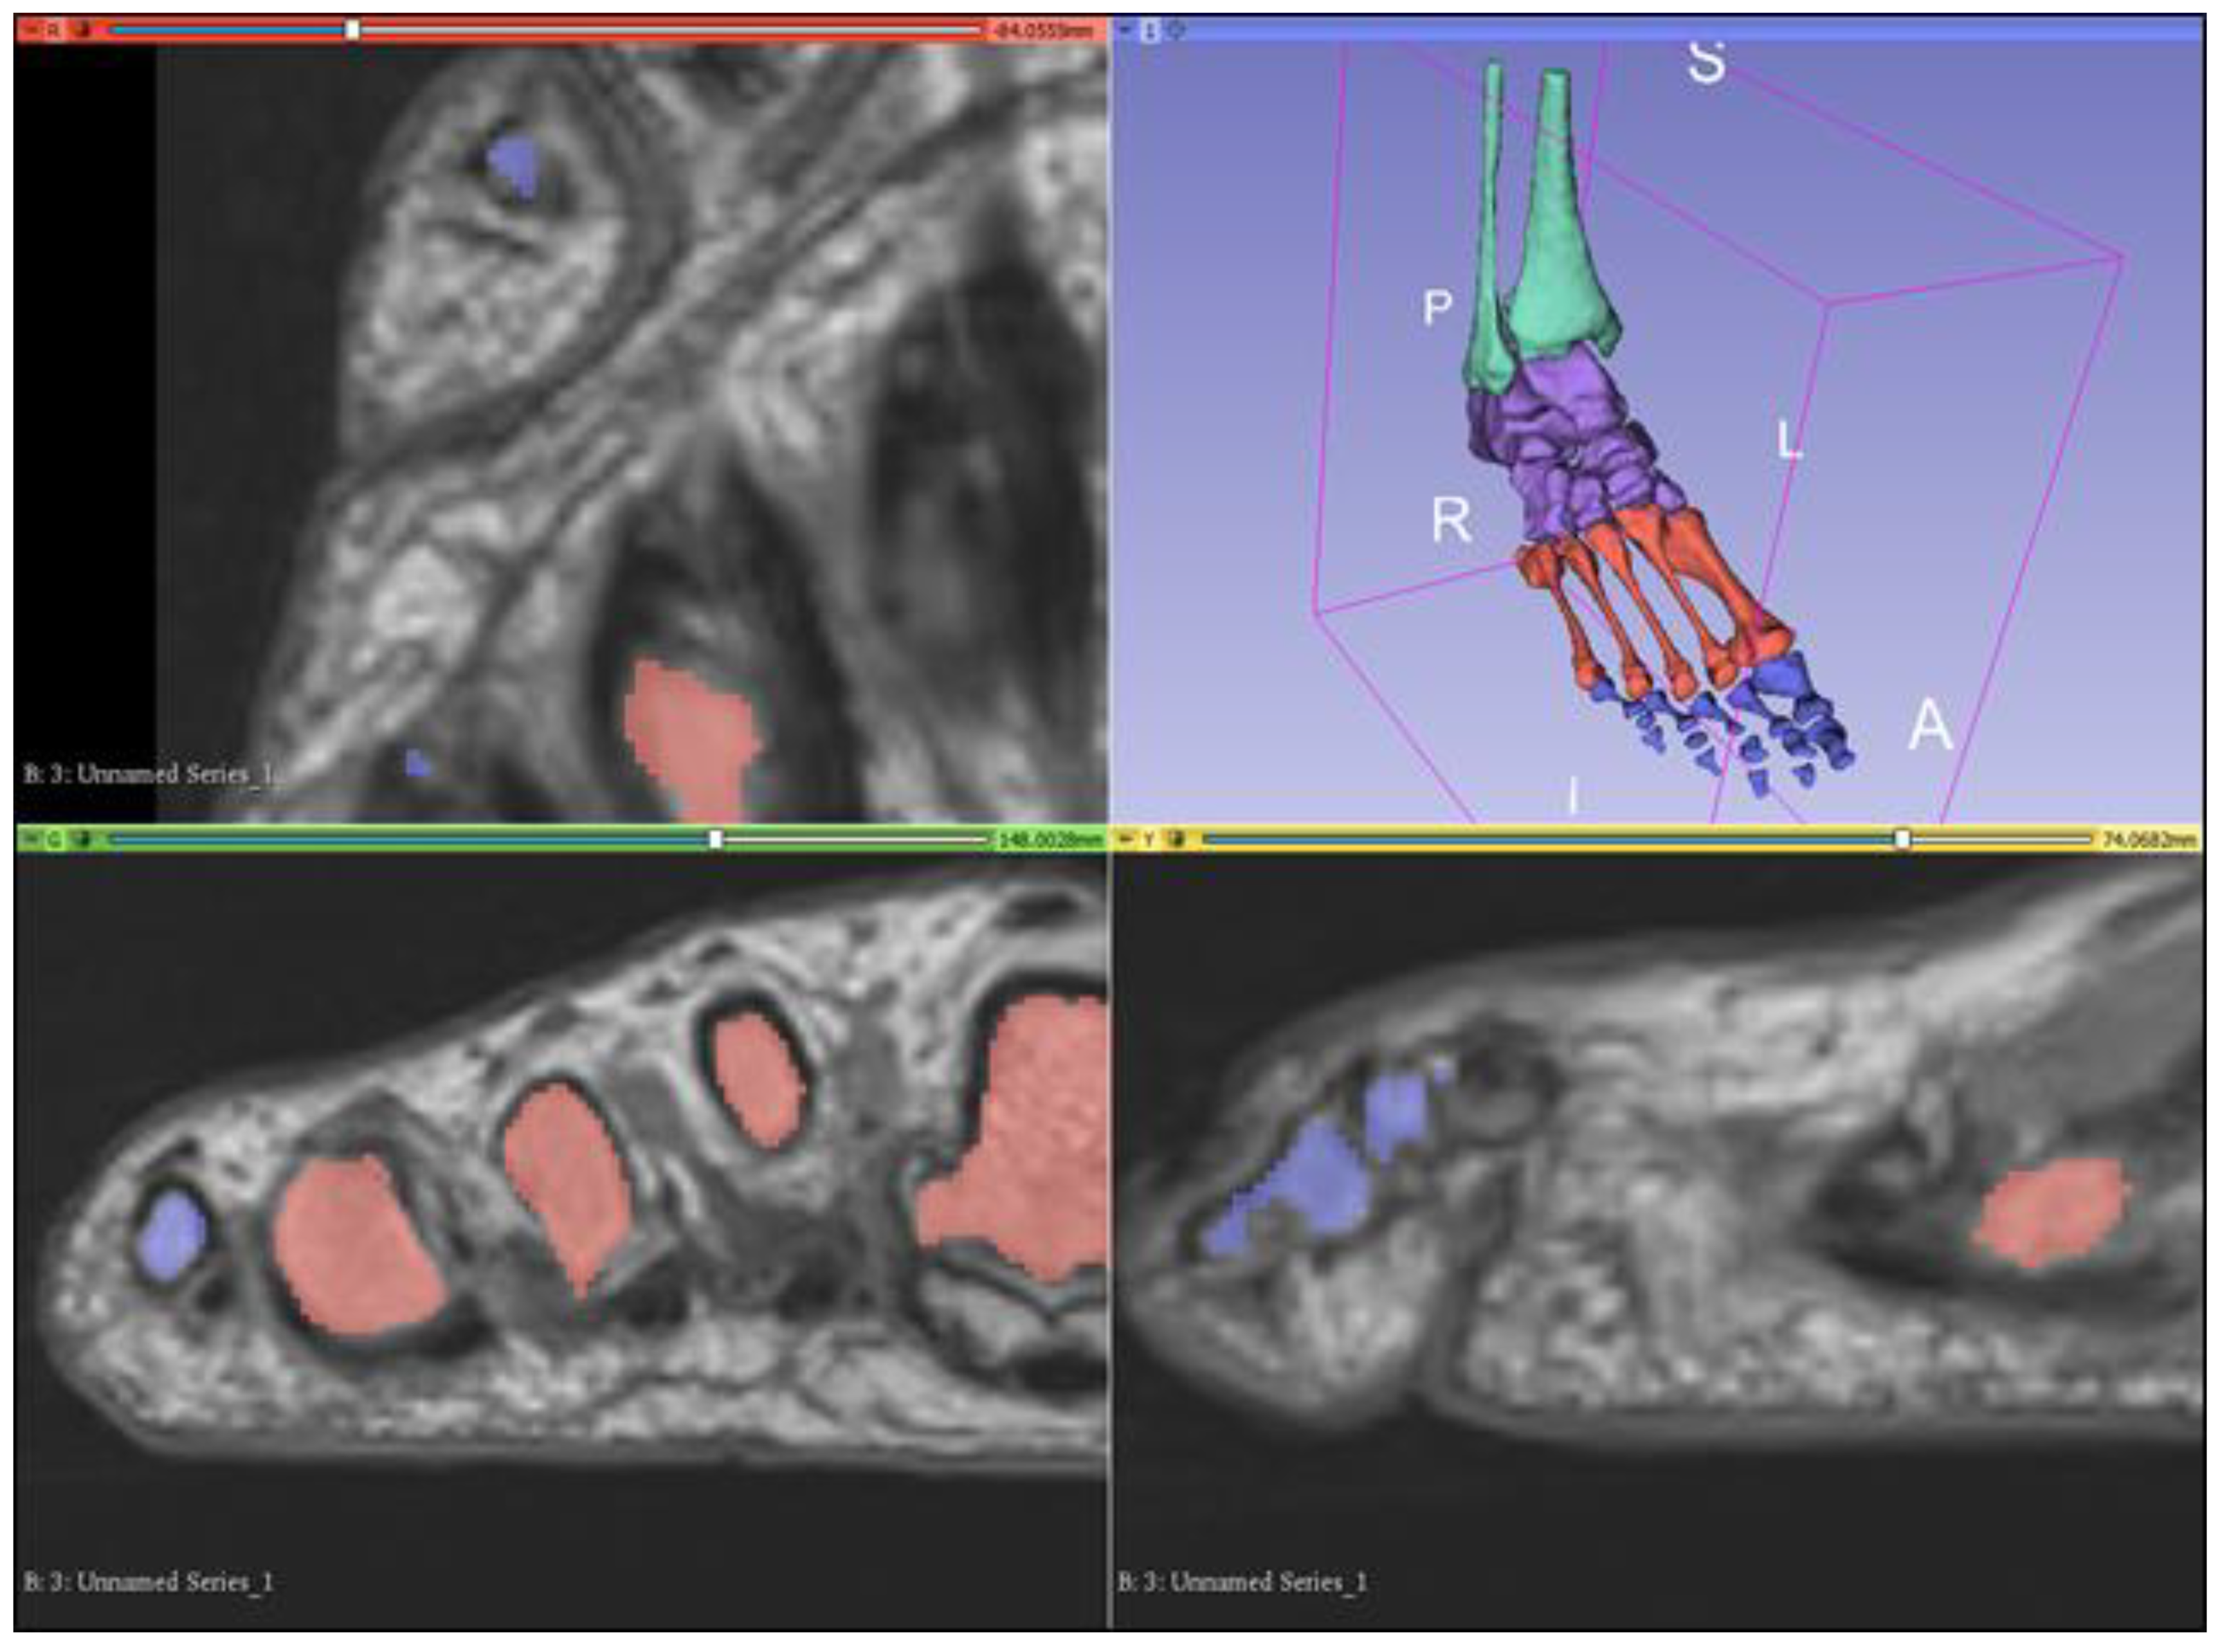

2.1. Image Processing and Segmentation of MRI Dataset Using 3D Slicer

2.2. Segmentation of Bony Anatomy

2.3. Segmentation of Musculature